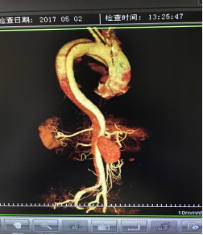

5月2號劉大伯照常早起干活,突然胸部劇烈疼痛,難以忍受,全身大汗,同時伴有右上肢發(fā)涼,他心想這次心絞痛比之前嚴重的多啊,趕緊叫上孩子到吉林國文醫(yī)院心血管內(nèi)科住院,患者長期高血壓病史,血壓一直控制不理想,大夫給他做了檢查,測左上肢血壓:82/45mmHg,右上肢血壓測不出,心率52次/分,右側(cè)肱動脈、尺動脈、橈動脈搏動消失,左側(cè)股動脈搏動較右側(cè)弱?!霸懔耍p側(cè)血壓差別這么大,是不是主動脈夾層了?”,接診大夫趕緊找來李主任,李主任反復詢問患者病情,表情突然凝重起來,患者胸痛這么明顯,血壓低的厲害,主動脈夾層的可能性很大。二話不說,李主任立即聯(lián)系影像科的醫(yī)生準備做主動脈CTA,移動患者做檢查的過程大夫們非常小心,嚴密監(jiān)測患者血壓變化情況。兩個小時后結(jié)果出來了,主動脈夾層從升主動脈一直撕裂到左側(cè)髂總動脈!??!

李主任詳細的與劉大伯的女兒交代了病情,手術(shù)是挽救生命的唯一辦法,為了劉大伯的一線生機,我們積極聯(lián)系了我省權(quán)威的心血管外科,并做了詳細的匯報,兩家醫(yī)院對此非常重視,為劉大伯開通了綠色通道,安全的把他總到上級醫(yī)院,當天便給他進行血管置換及覆膜支架植術(shù)。他術(shù)后恢復的很好,后來劉大伯的女兒看望我們,感嘆道:沒想到國文醫(yī)院心內(nèi)科應急能力這么高,在那么短的時間內(nèi)診斷明確,才給了我的老父親手術(shù)的機會。